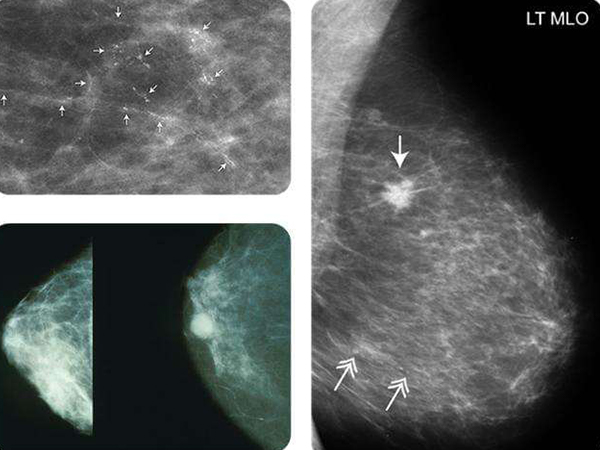

乳腺增生是乳腺在发育和退化中失常导致的一种良性病变,而导致该病变的主要因素是因为激素分泌失调,本质上是乳腺主质和间质的增生及复旧不全导致的结构紊乱,而不同类型的增生是单独存在,也可同时出现在一侧乳腺的小叶内,甚至存在不同小叶增生不一样的情况。

乳腺增生是一种女性良性乳腺疾病,一般来说对女性的健康没有太大的危害,但是也有非常小概率的几率会演变成乳腺癌,因此在检查出乳腺增生后也要引起一定的重视,而引起乳腺增生形成的原因主要是因为内分泌功能紊乱,同时还会受到多个因素的影响。

乳腺增生是女性常见的一种疾病,对女性来轻度的乳腺增生不会影响身体健康和生活方式,但是会产生乳腺疼痛,结节或者肿块,部分患者还存在溢液的情况,而形成这种乳腺增生的原因主要是因为内分泌失调,主要与四项激素有关,分别是:

1雌激素和孕激素比例失调,导致乳腺实质增生过度和恢复不全;2乳腺性激素受体的质和量都表示异常,导致了乳腺各部分增生程度不同;3催乳素升高,影响乳腺生长、发育和泌乳功能,同时还影响下丘脑-垂体-性腺轴功能。

以上三点就是引发乳腺增生的原因,也是导致乳腺增生的变化过程,而除了上述三点因素,还有一些因素也会诱发乳腺增生,比如说年龄、孕育史、哺乳史、月经史、避孕药服药史、社会心理因素等等,这些因素都会导致性激素或其受体改变,因此有增加乳腺增生的风险。